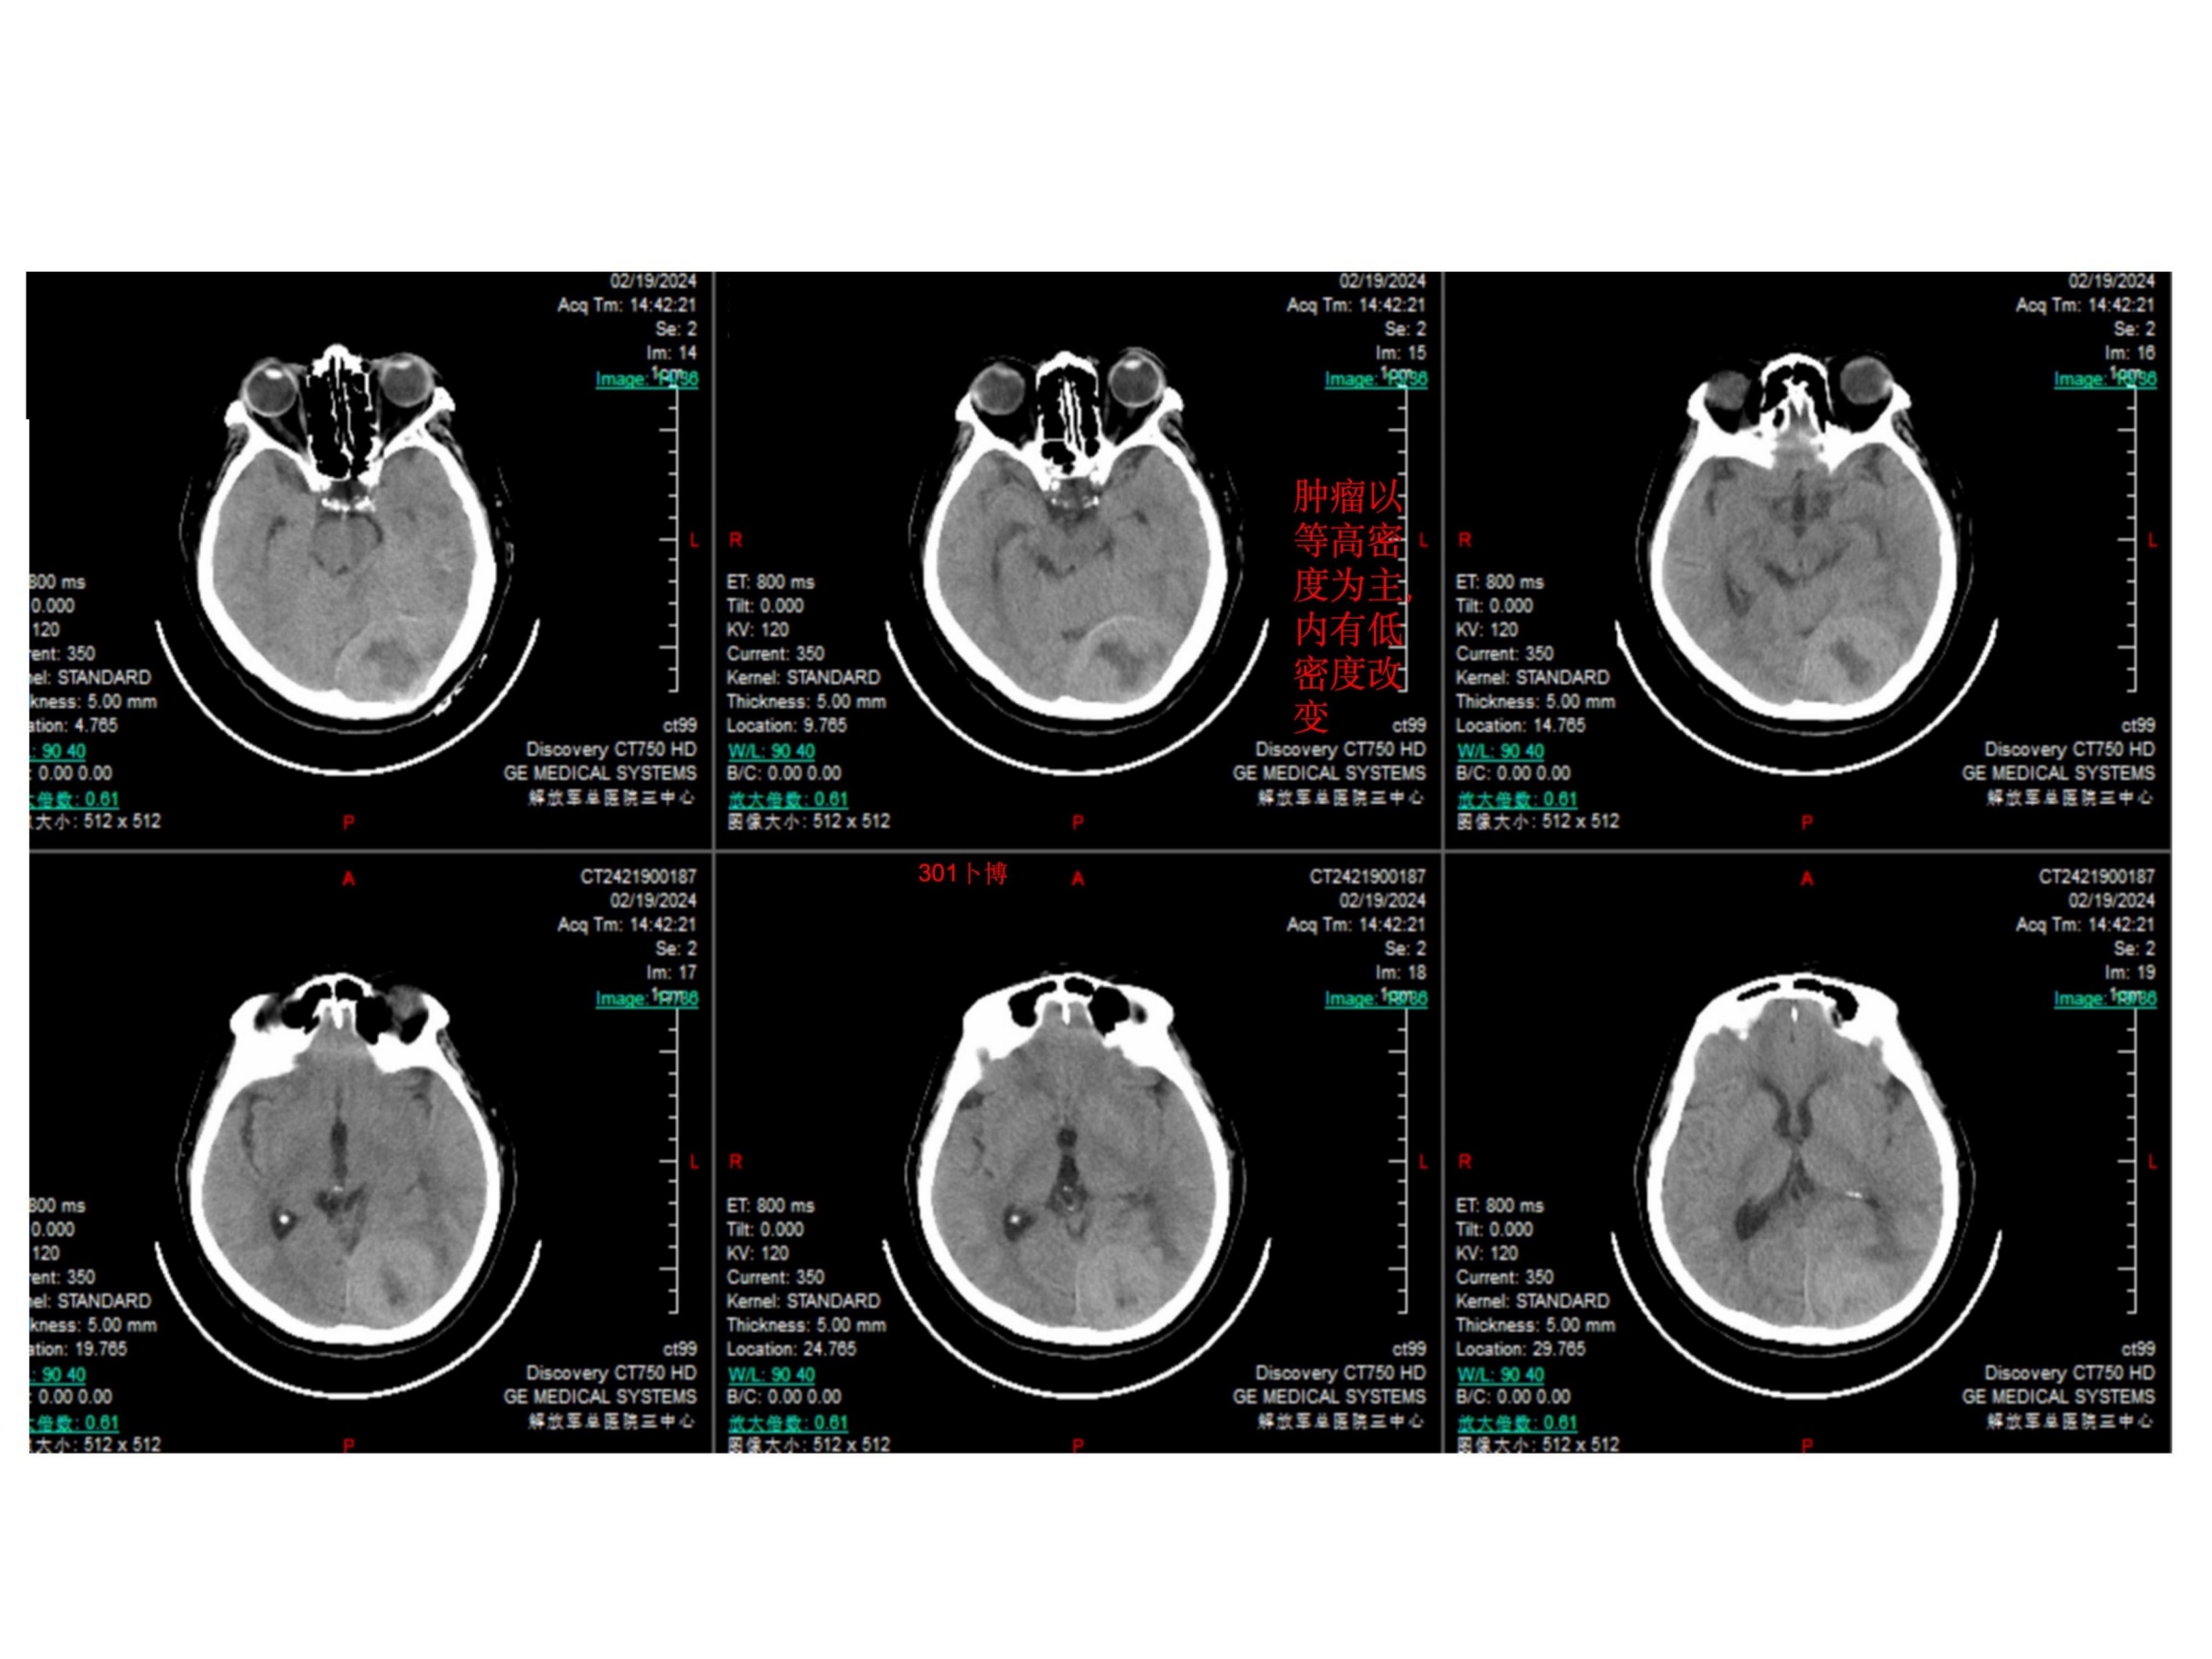

患者主要表现为双眼视力下降一个月余,加重3周。患者1个月前无明显诱因出现双眼视力下降伴视物重影,就诊当地医院行眼科相关检查,未能发现病因。3周前患者因头晕就诊徐州市中心医院,行头部CT提示颅内占位,进一步行头部磁共振检查提示脑膜瘤可能,建议手术治疗。1周前来我院就诊。查体:视力双眼0.6,右侧颞侧同向偏盲。眼底视乳头水肿。余神经系统查体阴性。诊断考虑为小脑幕-横窦-窦汇区脑膜瘤(侵袭性、WHO级,或者孤立纤维瘤)。手术前行栓塞两次,栓掉了大部分血供,同时看到左侧横窦闭塞,窦汇区通畅,静脉引流至对侧。手术采用俯卧位,导航下确认上矢状窦和窦汇区的位置。横窦已闭塞。中线旁跨横窦骨瓣。骨瓣已被肿瘤穿透。以上矢状窦后部为中心,星状剪开硬膜。抬起枕叶切除肿瘤以及受累及的横窦(已闭)小脑幕,向前(术野深面)切除至正常小脑幕边缘,幕间窦发达,一一电凝之。外侧结扎横窦乙状窦移行处,局部取枕部肌肉缝合加固,注意保护labbe静脉汇入点。向内导航下确认窦汇区的边缘。局部结构混乱,窦壁、大脑镰和小脑幕不通程度受累,正常窦壁侵犯无法准确辨认,只能导航确认一下边界。而且肿瘤充分切除减压以后局部膨隆,随呼吸节律波动,考虑窦壁菲薄。理想状态是切除受累及的窦壁并修补(见手绘文献图片)。考虑其为全脑静脉血管的最主要回流通道,没有准备好血管分流管,故未进一步切除受侵犯的窦壁。肿瘤次全切除。病理报告为孤立纤维瘤。术后三个月MRI增强提示切除理想,窦壁略增厚。建议补充伽马刀治疗。

CT为等密度占位,内有低密度改变,可能为坏死灶。肿瘤边缘清楚。